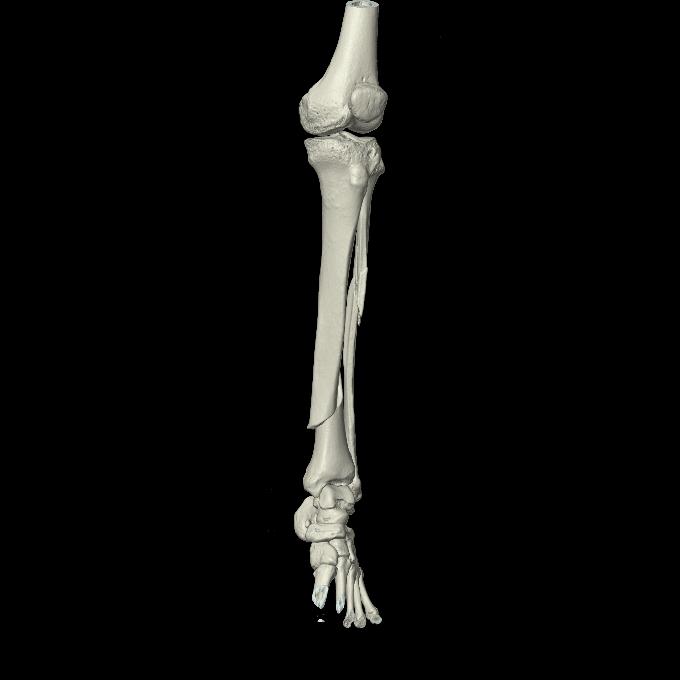

102803 1/12(キウスなし) 1/27 左下腿 4R 30歳女性 左脛骨軸内釘